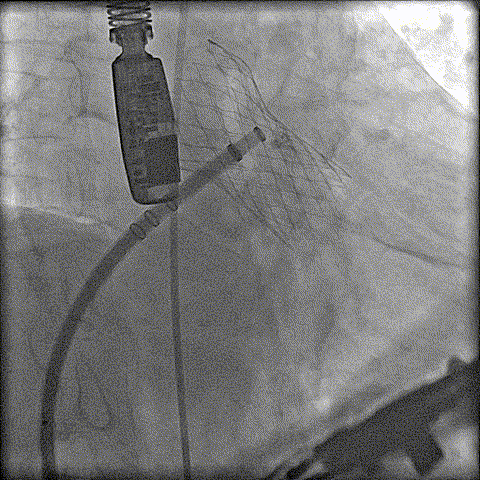

预扩

猪尾中部释放

稳定回收

评估

最终释放

后扩

无瓣周漏